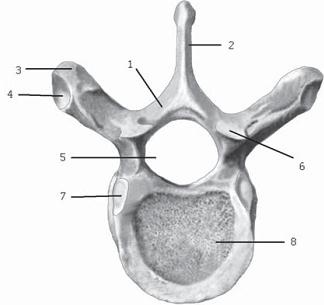

![]() Фото № 1. Макет, шейного отдела позвоночника человека, на котором хорошо видно, как позвоночная артерия проходит через отверстия в поперечных отростках, образующих таким образом костный канал для позвоночной артерии. Есть в шейном отделе позвоночника и свои «оперуполномоченные» — суставные отростки, которые принимают участие в формировании дугоотростчатых суставов. А поскольку суставные поверхности на этих отростках расположены ближе к горизонтальной плоскости, то в совокупности это значительно расширяет возможности шейного отдела позвоночника, обеспечивает более эффективную подвижность головы, позволяет достигать большего угла скручивания. Однако последнее как раз и стало уязвимым местом для шейного отдела, учитывая небольшую прочность шейных позвонков, их вес и степень подвижности. Как говорится, даже у «особого отдела» есть своя «ахиллесова пята». Обнаружить же, где именно заканчиваются пределы вашего «особого отдела», вы можете по седьмому шейному позвонку. Дело в том, что длина остистых отростков (кстати, концы их раздвоены, кроме VII) увеличивается от II к VII позвонку. Остистый отросток седьмого шейного позвонка самый длинный и к тому же утолщён на конце. Он является весьма заметным анатомическим ориентиром: при наклоне головы на задней поверхности шеи хорошо прощупывается верхушка наиболее выступающего остистого отростка. Кстати, данный позвонок так и называется по-латыни vertebra prominens — позвонок выступающий. Это и есть та самая легендарная «семёрка», благодаря которой можно сосчитать ваши позвонки с диагностической точностью. Грудной отдел позвоночника состоит из 12 позвонков. Латинское название vertebrae thoracicae — позвонки грудные. Латинское слово thorax — грудная клетка — образовано от греческого слова thoraks — грудь. В медицинских документах позвонки грудного отдела обозначаются как «ТЬ> или «Т». Высота тел данных позвонков постепенно возрастает от I до XII позвонка. Остистые отростки накладываются друг на друга черепицеобразно, прикрывая дуги нижележащих позвонков. МРТ № 2 ![]() На МРТ № 2 — грудной отдел в состоянии «норма» Грудной отдел должен иметь нормальную степень кифоза (угол кифоза по Stagnara формируется линией, параллельной замыкательным пластинкам ТIII и ТXI= 25°). Позвоночный канал на грудном уровне имеет округлую форму, что делает эпидуральное пространство узким почти по всей окружности дурального мешка (0,2–0,4 см), а на участке между TVI и ТIX он наиболее узок. Сагиттальный размер: ТI-ТХI = 13–14 мм, ТXII = 15 мм. Поперечный диаметр: > 20–21 мм. Высота межпозвонковых дисков: самая меньшая на уровне ТI, на уровне ТVI-ТХI приблизительно 4-5 мм, наибольшая на уровне ТХI-ТХII. Также характерным признаком для большинства грудных позвонков является наличие на боковых поверхностях тел верхней и нижней рёберных ямок для сочленения с головками рёбер, а также наличие рёберной ямки на поперечных отростках для соединения с бугорком ребра. Из-за специфики своей конструкции, небольшой высоты межпозвонковых дисков этот отдел, безусловно, не столь подвижен, как шейный отдел. Однако и предназначен он для других целей. Позвонки грудного отдела в совокупности с грудными рёбрами, грудиной образуют костную основу верхней части туловища — грудную клетку, которая является опорой для плечевого пояса, вместилищем жизненно важных органов. Она позволяет использовать межрёберную мускулатуру при дыхательных движениях. Соединение грудных позвонков с рёбрами придаёт этому отделу позвоночника большую жёсткость благодаря рёберному каркасу грудной клетки. Так что эти позвонки можно образно сравнить с людьми, слаженно и эффективно работающими в одной большой команде, чётко исполняющими свои функции и обязанности. ![]() Рисунок № 11. Грудной позвонок. Вид сверху 1 — дуга позвонка; 2 — остистый отросток; 3 — поперечный отросток; 4 — рёберная ямка поперечного отростка; 5 — позвоночное отверстие; 6 — верхний суставной отросток; 7 — верхняя рёберная ямка; 8 — тело позвонка Поясничный отдел позвоночника составляют 5 самых крупных позвонков, имеющих массивные, бобовидной формы тела позвонков, прочные отростки. Высота и ширина тел позвонков постепенно увеличиваются от первого до пятого позвонка. Латинское название vertebrae lumbales — позвонки поясничные, лат. lumbalis — поясница. Соответственно обозначаются: первый поясничный позвонок — Lp второй поясничный позвонок — LII и так далее. Подвижный поясничный отдел позвоночника соединяет малоподвижный грудной отдел с неподвижным крестцом. Это самые настоящие «трудяги», которые мало того, что испытывают значительное давление со стороны верхней части тела, так ещё и по жизни подвергаются серьёзной дополнительной нагрузке, о которой было частично сказано в предыдущей главе. МРТ № 3